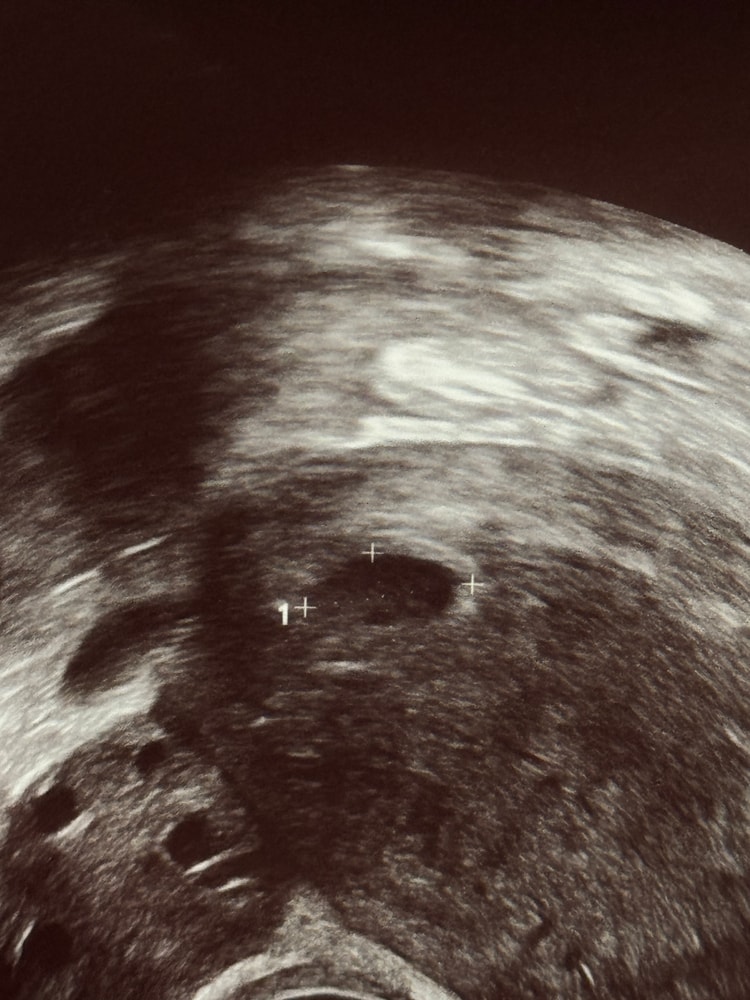

УЗИ, КТГ, доплерДевушки, посмотрите, пожалуйста, на узи внизу ПЯ это желточный мешочек?

а то узи как-то не очень сделали, не сказали, есть ли жм, ПЯ примерно 10 мм.